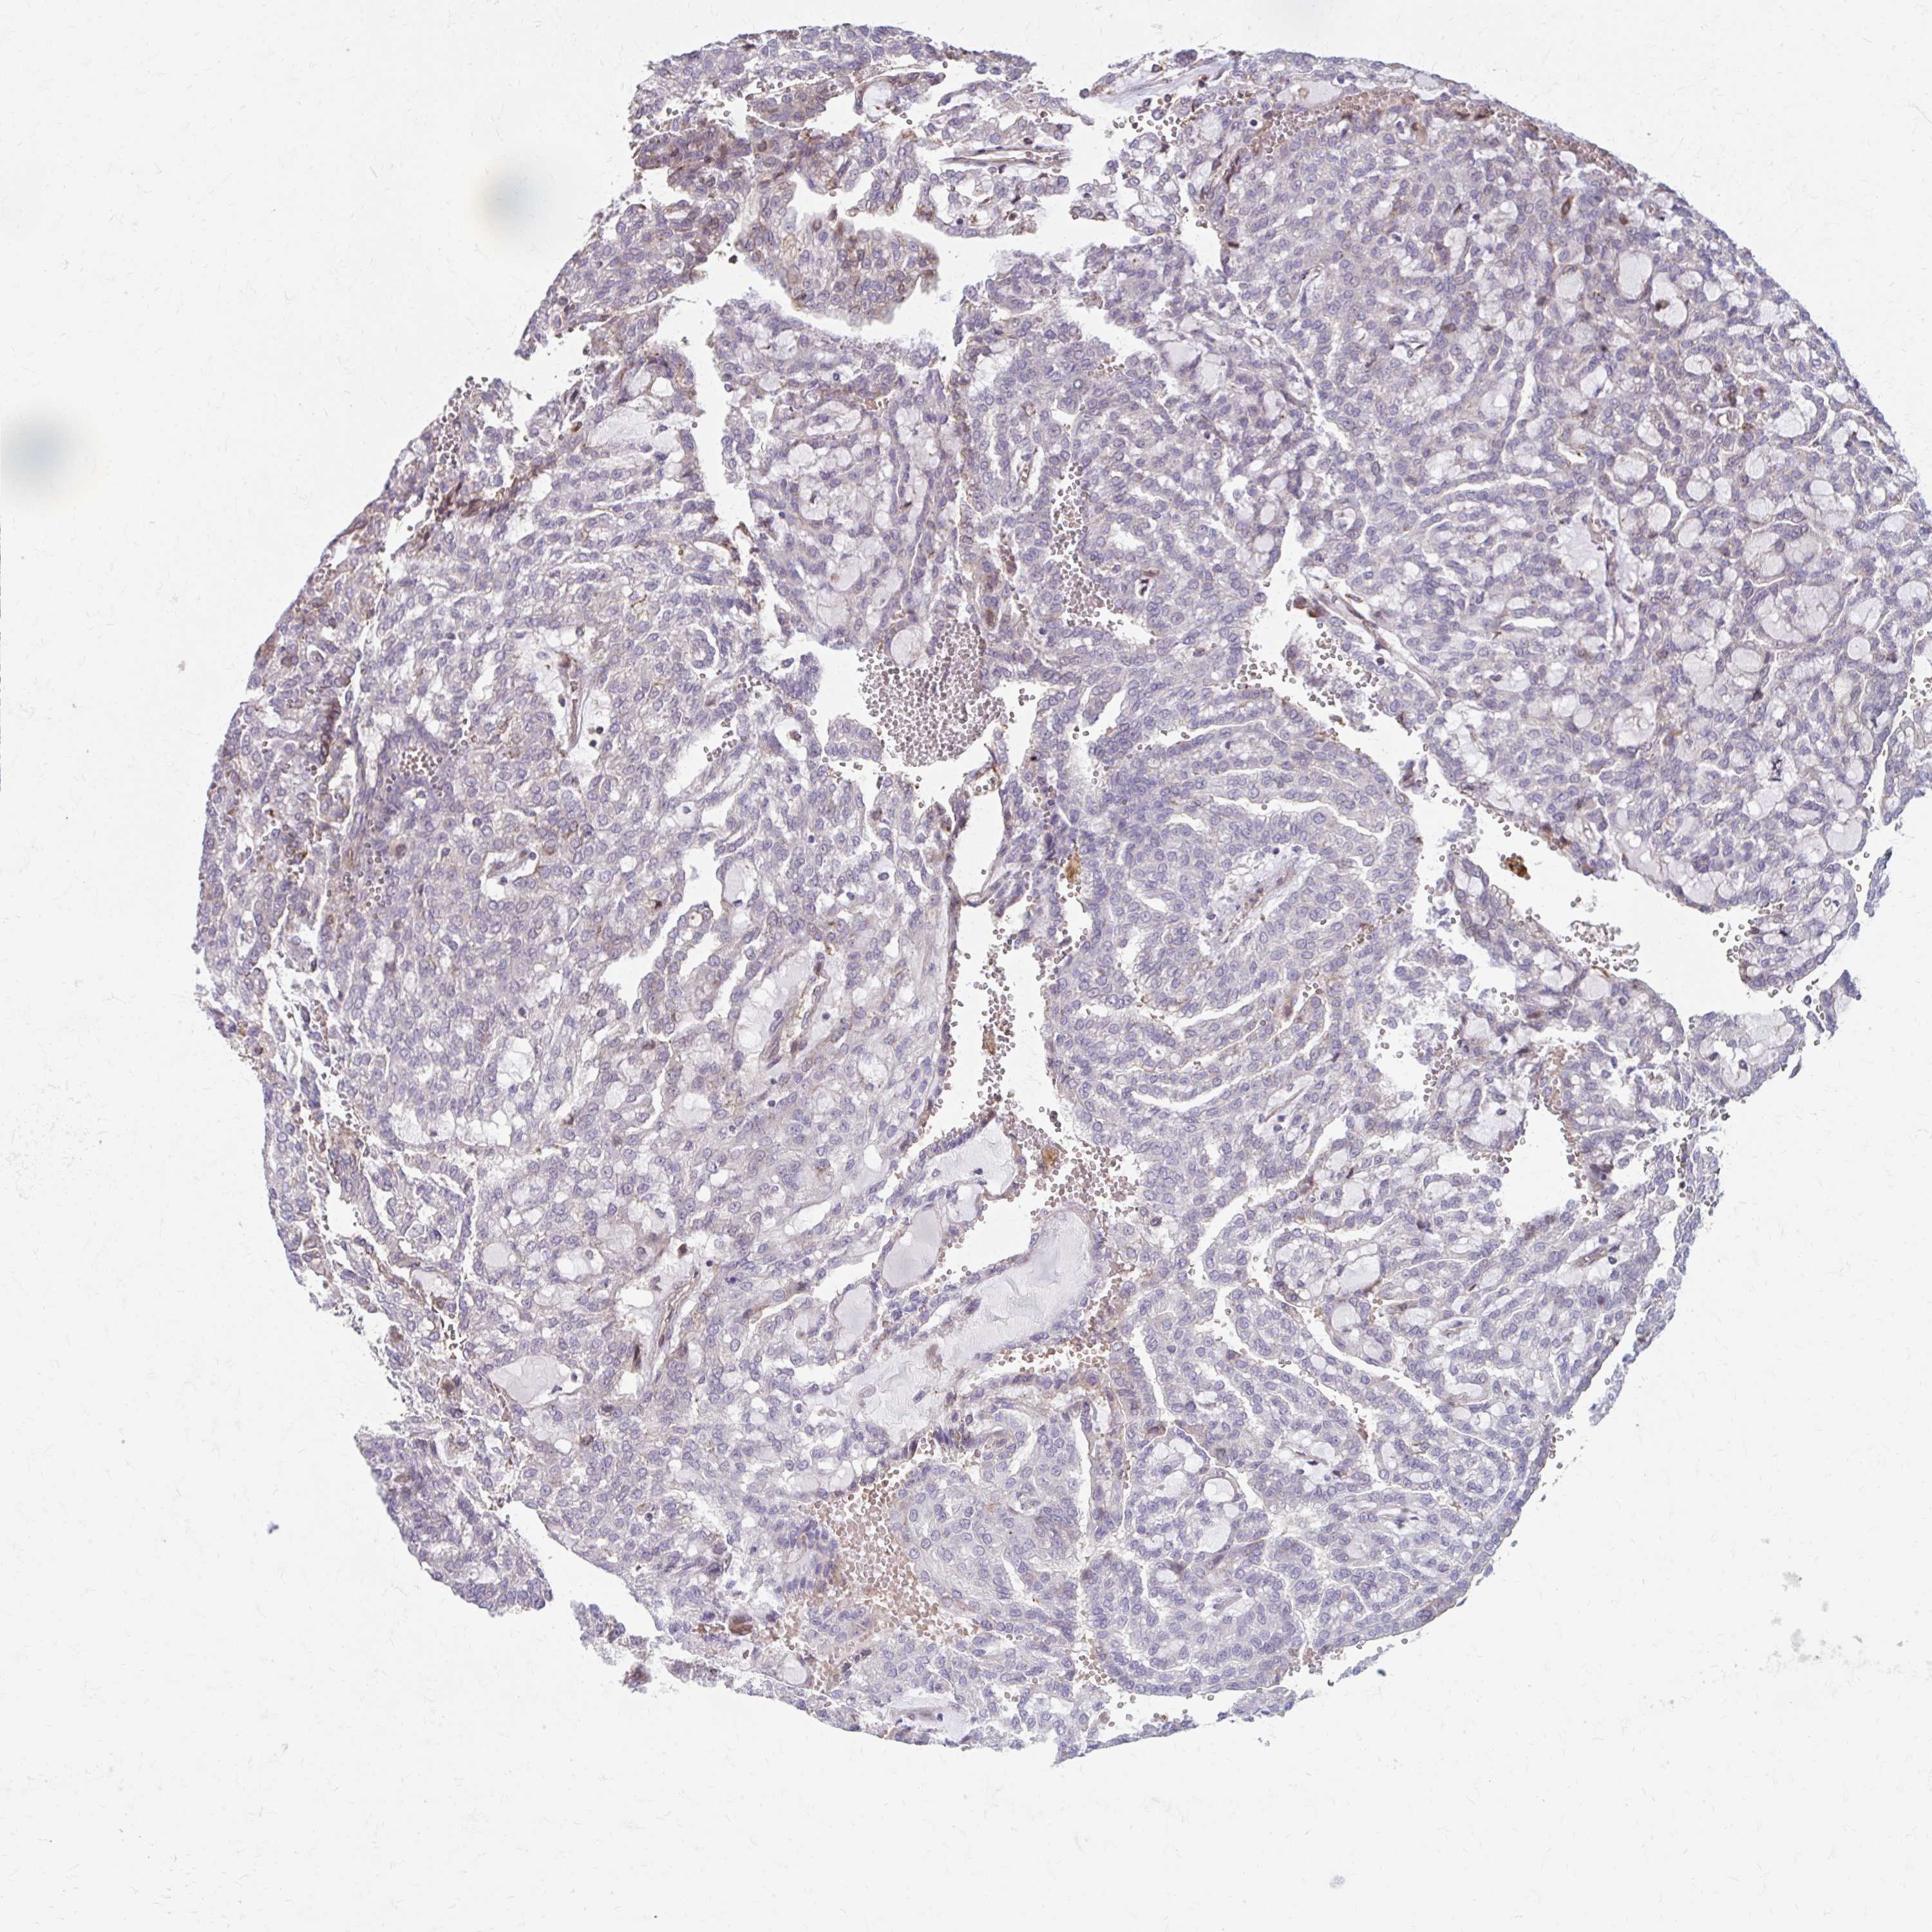

CANCER RENAL CANCER Show tissue menu

KICH TCGA KIRC TCGA KIRC VALIDATION KIRP TCGA PROTEIN RCC CPTAC PROTEIN EXPRESSION